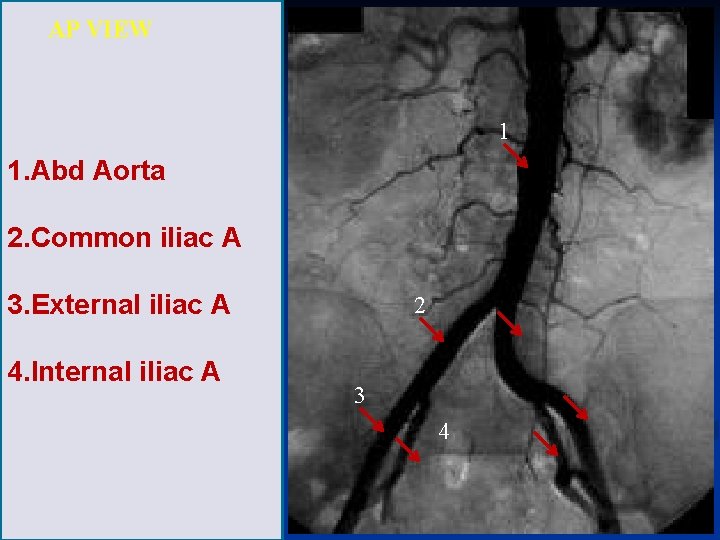

AP VIEW 1 1. Abd Aorta 2. Common iliac A 3. External iliac A 4. Internal iliac A 2 3 4